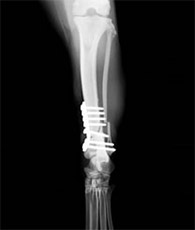

後足大腿骨骨折

このタイプはそう簡単に骨折する場所ではありませんが、いちど骨折すると筋肉が一番多い場所なので、整復手術するのに手間がかかります。

手術前

手術後

ラブラドールの交通事故による左大腿骨骨折です。体重も重く、動きも激しい犬種なので、かなり強固な固定が必要でした。髄内ピン+プレート固定により治療を行いました。